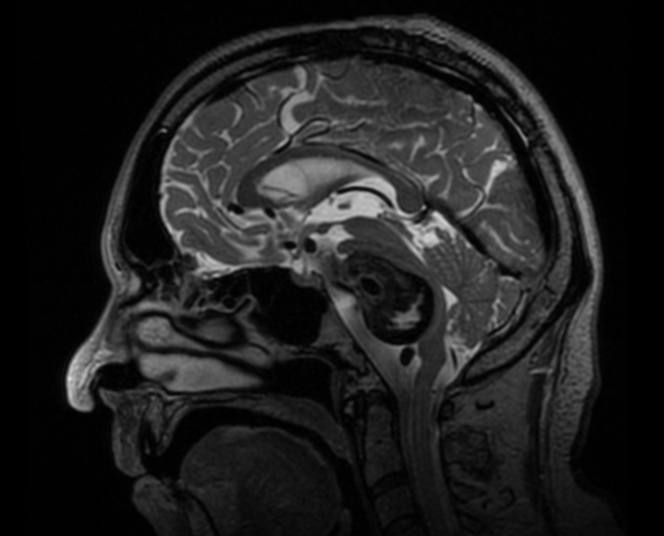

MRI scan of a human brain with giant Basilar artery aneurysm

A Hemorrhagic stroke occurs when a blood vessel ruptures within or around the brain, causing bleeding that damages neural tissue and disrupts cerebrospinal fluid circulation. Unlike ischemic strokes, which result from vessel occlusion, hemorrhagic strokes often strike younger individuals and lead to higher mortality and long-term disability.

The most common causes are intracranial aneurysms, arteriovenous malformations (AVMs), cerebral cavernous malformations (CCMs), and dural arteriovenous fistulas (DAVFs) — as well as spontaneous intracerebral hemorrhage related to hypertension or small-vessel disease. These vascular anomalies can rupture suddenly, leading to life-threatening bleeding such as: